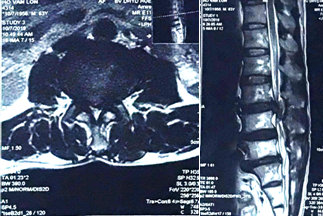

Hình 1. MRI tầng L3/L4: thoát vị đĩa đệm L3/4 chèn ép chùm đuôi ngựa.

Tại thời điểm nhập viện, bệnh nhân có ý thức và mạch lạc. Các xét nghiệm cận lâm sàng bao gồm công thức máu cho thấy hồng cầu 3,7 T/l, bạch cầu 8,52 G/l, tiểu cầu 188 G/l, tổng phân tích nước tiểu, chức năng gan và thận, với mức triglyceride, cholesterol và axit uric bình thường. Creatinine huyết thanh 6,2 umol/L, ure huyết thanh 8,3 mmol/L. Chụp MRI (Hình 1) giảm tín hiệu nước các tầng đĩa đệm từ ngang mức L3. Tầng L3/L4: thoát vị rộng ra sau hướng xuống làm hẹp nặng ống sống (độ C), hẹp lỗ liên hợp hai bên, chèn ép chùm đuôi ngựa và rễ thần kinh tương ứng hai bên trong ống sống và ngách bên. Tầng L4/L5; phình đĩa đệm, chèn bao màng cứng làm hẹp ống sống (độ B), hẹp lỗ liên hợp bên trái, chưa thấy rõ chèn rễ thần kinh. Tầng L5/S1: thoát vị đĩa đệm trung tâm và cận phải, chèn ép bao màng cứng, chèn ép rễ thần kinh tương ứng bên phải đoạn trong ống sống. Bệnh nhân được chẩn đoán là hội chứng chùm đuôi ngựa và được lên lịch phẫu thuật mở bản sống rộng rãi, giải áp đoạn L3-L4, và cố định cột sống bằng vít qua cuống L3-L4 (Hình 2). Hậu phẫu không có biến chứng gì, bệnh nhân được xuất viện sau 10 ngày với cơ lực 2 chân được phục hồi, tuy nhiên rối loạn chức năng cơ vòng chưa cải thiện bệnh nhân được hướng dẫn đạt thông tiểu ngắt quãng. Sau 2 tháng, bệnh nhân tái khám với chức năng vận động được phục hồi gần như hoàn toàn, còn cảm giác căng tiểu và cảm giác đại tiện cải thiện rõ rệt với bệnh nhân có thể đại tiểu tiện được sau 3 tháng.